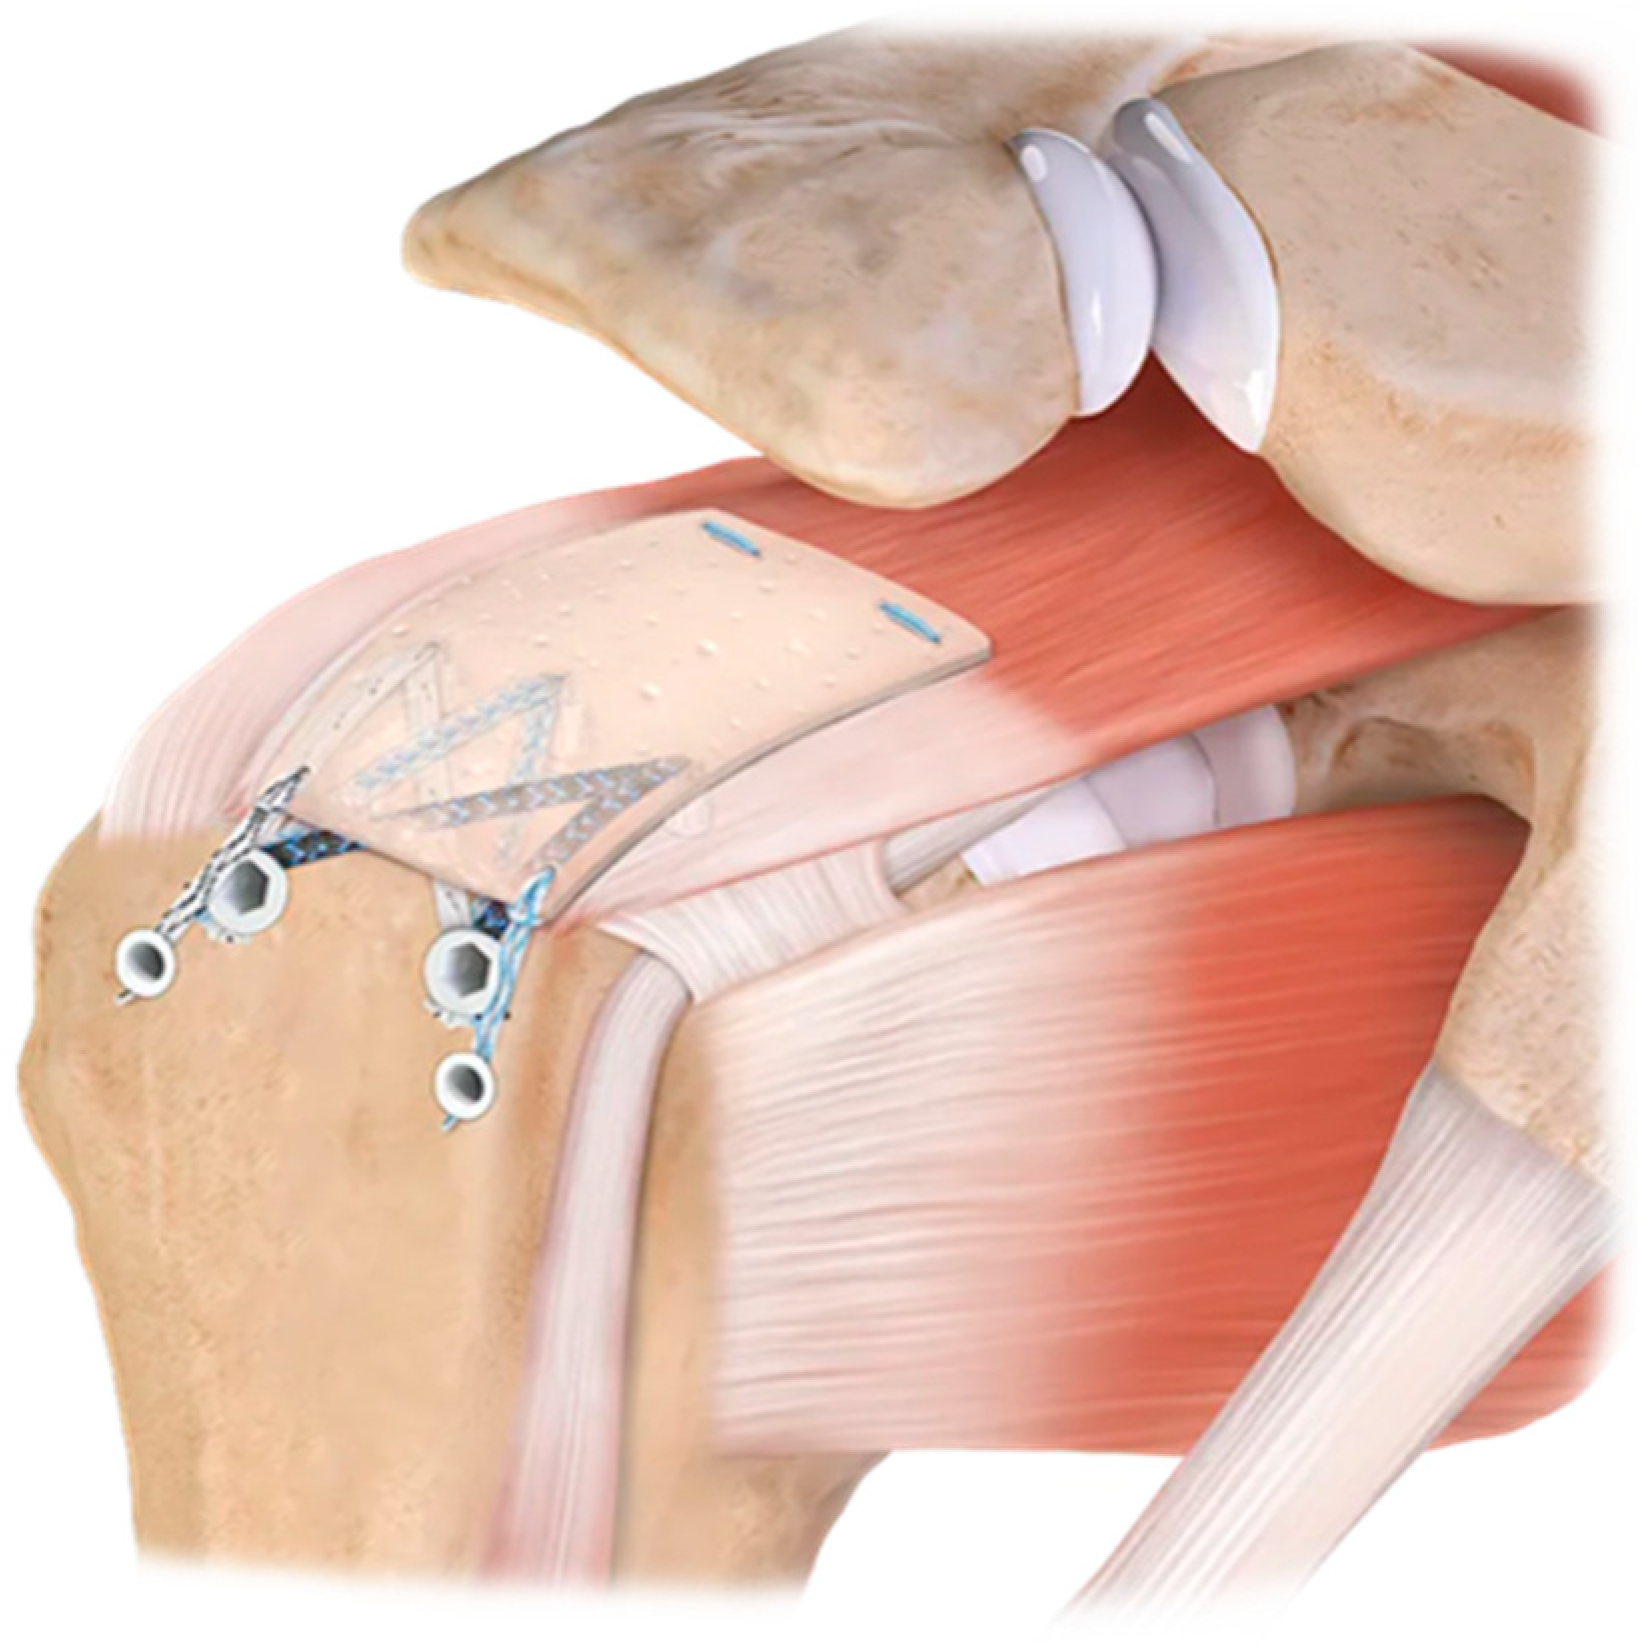

1.2. Augmentation vs. Interposition

3.1.4. The Future of Patch Augmentation